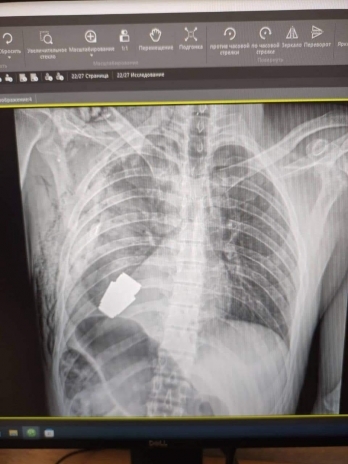

Украинские военные врачи удалили из тела военнослужащего неразорвавшуюся гранату ВОГ.

Операция продолжалась в присутствии двух саперов, контролировавших безопасность медицинского персонала и пациента, сообщает Генштаб ВСУ.

— Один из опытнейших хирургов ВСУ, генерал-майор Андрей Верба, работал без электрокоагуляции, поскольку граната могла детонировать в любой момент. Оперативное вмешательство прошло успешно, а раненого военнослужащего отправили на дальнейшую реабилитацию и восстановление, говорится в сообщении.